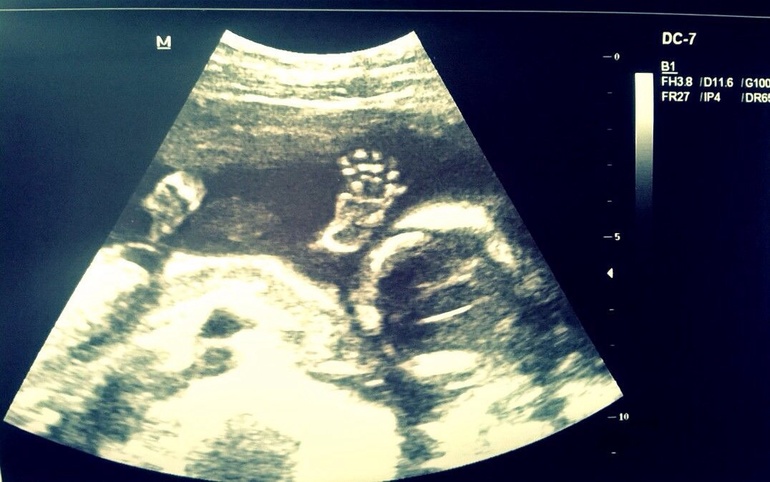

Заканчивая пяточкой (хотя по мне так больше на ручку похоже

)

Малыш показал все... И разрушил мои мечты о девочке... Как сказала врач: у вас растет 100% мужик... У девочек таких причиндалов не бывает